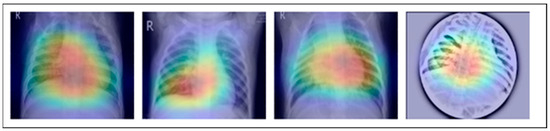

Along with infectious diseases, the diagnostic potential of DL models for lung cancer has also been thoroughly investigated. An image-based DL system can identify medical diagnoses, such as lung cancer. This model illustrated how DL may be used to detect the planned MixNet-LD system for the automatic identification and classification of lung diseases. The lungs are essential for the respiratory system, and they must function properly for the body to exchange oxygen and carbon dioxide. However, several illnesses can impact the lungs and have adverse health effects. Since it might be challenging to identify and extract the lesion characteristics connected to lung problems, early and precise diagnosis of lung diseases is crucial for prompt and effective therapy. To solve this problem, the MixNet-LD system combines the strength of MixNet, a particular pre-trained model, with dense blocks. By minimizing noise and emphasizing abnormalities, the suggested pre-processing technique utilizing Grad-Cam improves the quality of pictures of lung illness, further enhancing the classification’s performance. Data augmentation techniques are also used to correct the dataset’s class imbalance and avoid overfitting, strengthening, and improving the MixNet-LD model. The creation of the Pak-Lungs dataset, which consists of 6000 photos of lung diseases gathered from reliable online sources and Pakistani hospitals, is a significant addition to the study. The MixNet-LD model successfully handled various lung illness cases thanks to this sizable dataset, achieving a fantastic accuracy of 98.5% on the challenging lung disease dataset. Further demonstrating the superiority of the MixNet-LD system, which exceeds previous techniques with a substantially higher accuracy of 95%, is the comparison with state-of-the-art methods in medical image processing. As it offers a trustworthy and automated way of correctly diagnosing normal COVID-19, pneumonia, tuberculosis, and lung cancer illnesses, the system’s performance can potentially have real-world ramifications in medical diagnosis and therapy. Figure 13 represents the lung patterns detected by the MixNet-LD system and Figure 14 shows the visual results of the predicted MixNet-LD system.

Overall, the MixNet-LD method better presented state-of-the-art methods and performed well, making it an essential tool in medical image analysis. It can also handle a variety of lung disease scenarios. The MixNet-LD system can dramatically boost patient outcomes and healthcare management by delivering accurate and timely diagnostics of lung illnesses. Further investigation can look at the possibilities of the MixNet-LD system in various clinical contexts and the applicability of the technology to other medical image analysis jobs. The system’s breadth and influence in medical imaging may be increased by ongoing improvement and optimization, ultimately leading to more efficient medical image processing in clinical settings. Figure 13 demonstrates the compatibility of the m-Xception system with X-ray pictures, hence highlighting its potential benefits for significant biomedical applications. The illness-identified regions within images exhibit a higher level of effectiveness in the context of computer-aided diagnosis (CAD) systems, as they contribute to a streamlined process of disease classification when utilizing chest X-ray images.